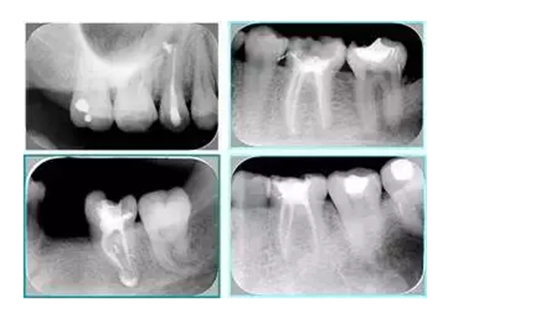

常見不良根管充填物有干髓、塑化、塑化 + 根充和不良根充。

( 1 )干髓。

干髓治療時(shí),開髓后髓腔里注入甲醛甲酚 FC 灌髓,三聚甲醛固定,髓室底放置三聚甲醛緩慢釋放,進(jìn)行根管無害化處理。髓腔緩慢壞死,機(jī)體代償出現(xiàn)根管鈣化。如果患者在封閉腔出現(xiàn)出現(xiàn)病變,由于髓腔鈣化,根管堵塞嚴(yán)重,檢查治療比較困難。

左圖和上圖為干髓治療后牙齒,齲齒疏通后進(jìn)行根管充填。

( 2 )塑化。

傳統(tǒng)的治療思維:塑化治療后患者需將塑化液清理干凈,達(dá)到徹底根管治療目的。

目前的治療思維:以前塑化治療效果好時(shí)不必清理干凈塑化液。對(duì)于根尖沒有病變的患者,可借助溶解劑建立通路;根尖存在病變的患者往往是塑化治療不理想患者,需要徹底打通通路。

( 3 )塑化 + 根充。

如圖為塑化加根充處理后牙齒 X 線片。

6. 鈣化

常見有修復(fù)性鈣化和增齡性鈣化。下面為根管鈣化 X 線片。

解決方法: ( 1 )清楚根管系統(tǒng)解剖形態(tài)。 ( 2 )安全頭的金剛砂鉆開髓,低速球鉆磨除鈣化牙本( ET20 ,ET40 ,DG-16 )。 ( 3 )徹底去除髓腔周壁的牙本質(zhì)齡。 ( 4 )借助化學(xué)性藥劑,如EDTA 等。